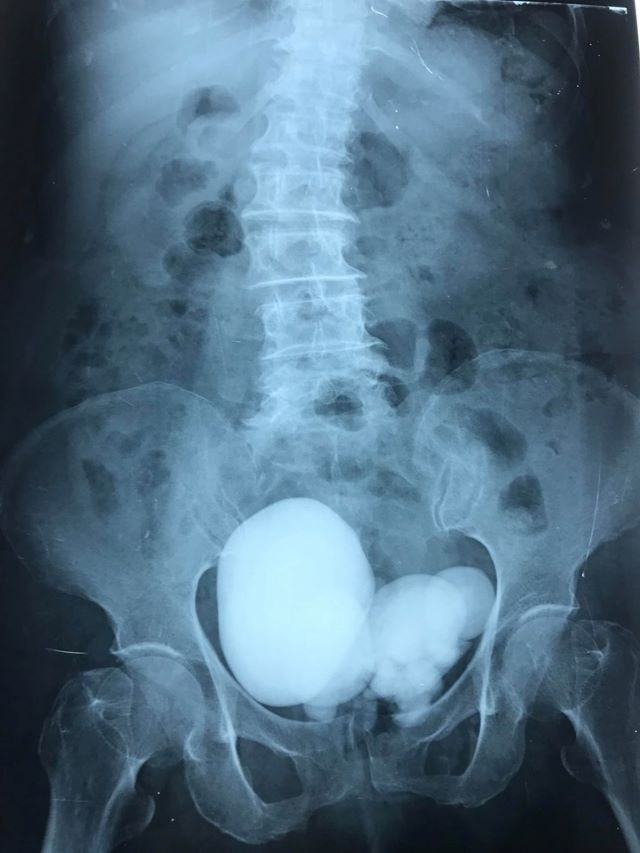

Kết quả siêu âm bụng cho thấy bệnh nhân có sỏi bàng quang to, chụp X-Quang và CTScan thấy thận (P) ứ nước độ I, niệu quản (P) dãn đến bàng quang, rất nhiều sỏi chiếm hết lòng bàng quang, trong có một viên sỏi nằm cạnh phải bàng quang to khoảng 12cm nằm trong túi thừa bàng quang, thận (P) ứ nước độ I nhu mô thận (P) còn dầy.

| Hình ảnh phim chụp (BVCC). |

Đặc biệt có một viên sỏi rất to khoảng 12 cm nằm trong một túi thừa bên phải, cạnh bàng quang đè lên niệu quản vùng chậu phải, gây ứ nước thận, mô xung quanh túi thừa rất dính do viêm, bóc tách túi thừa lấy viên sỏi 12cm ra bên trong có ít mủ và cặn trắng.